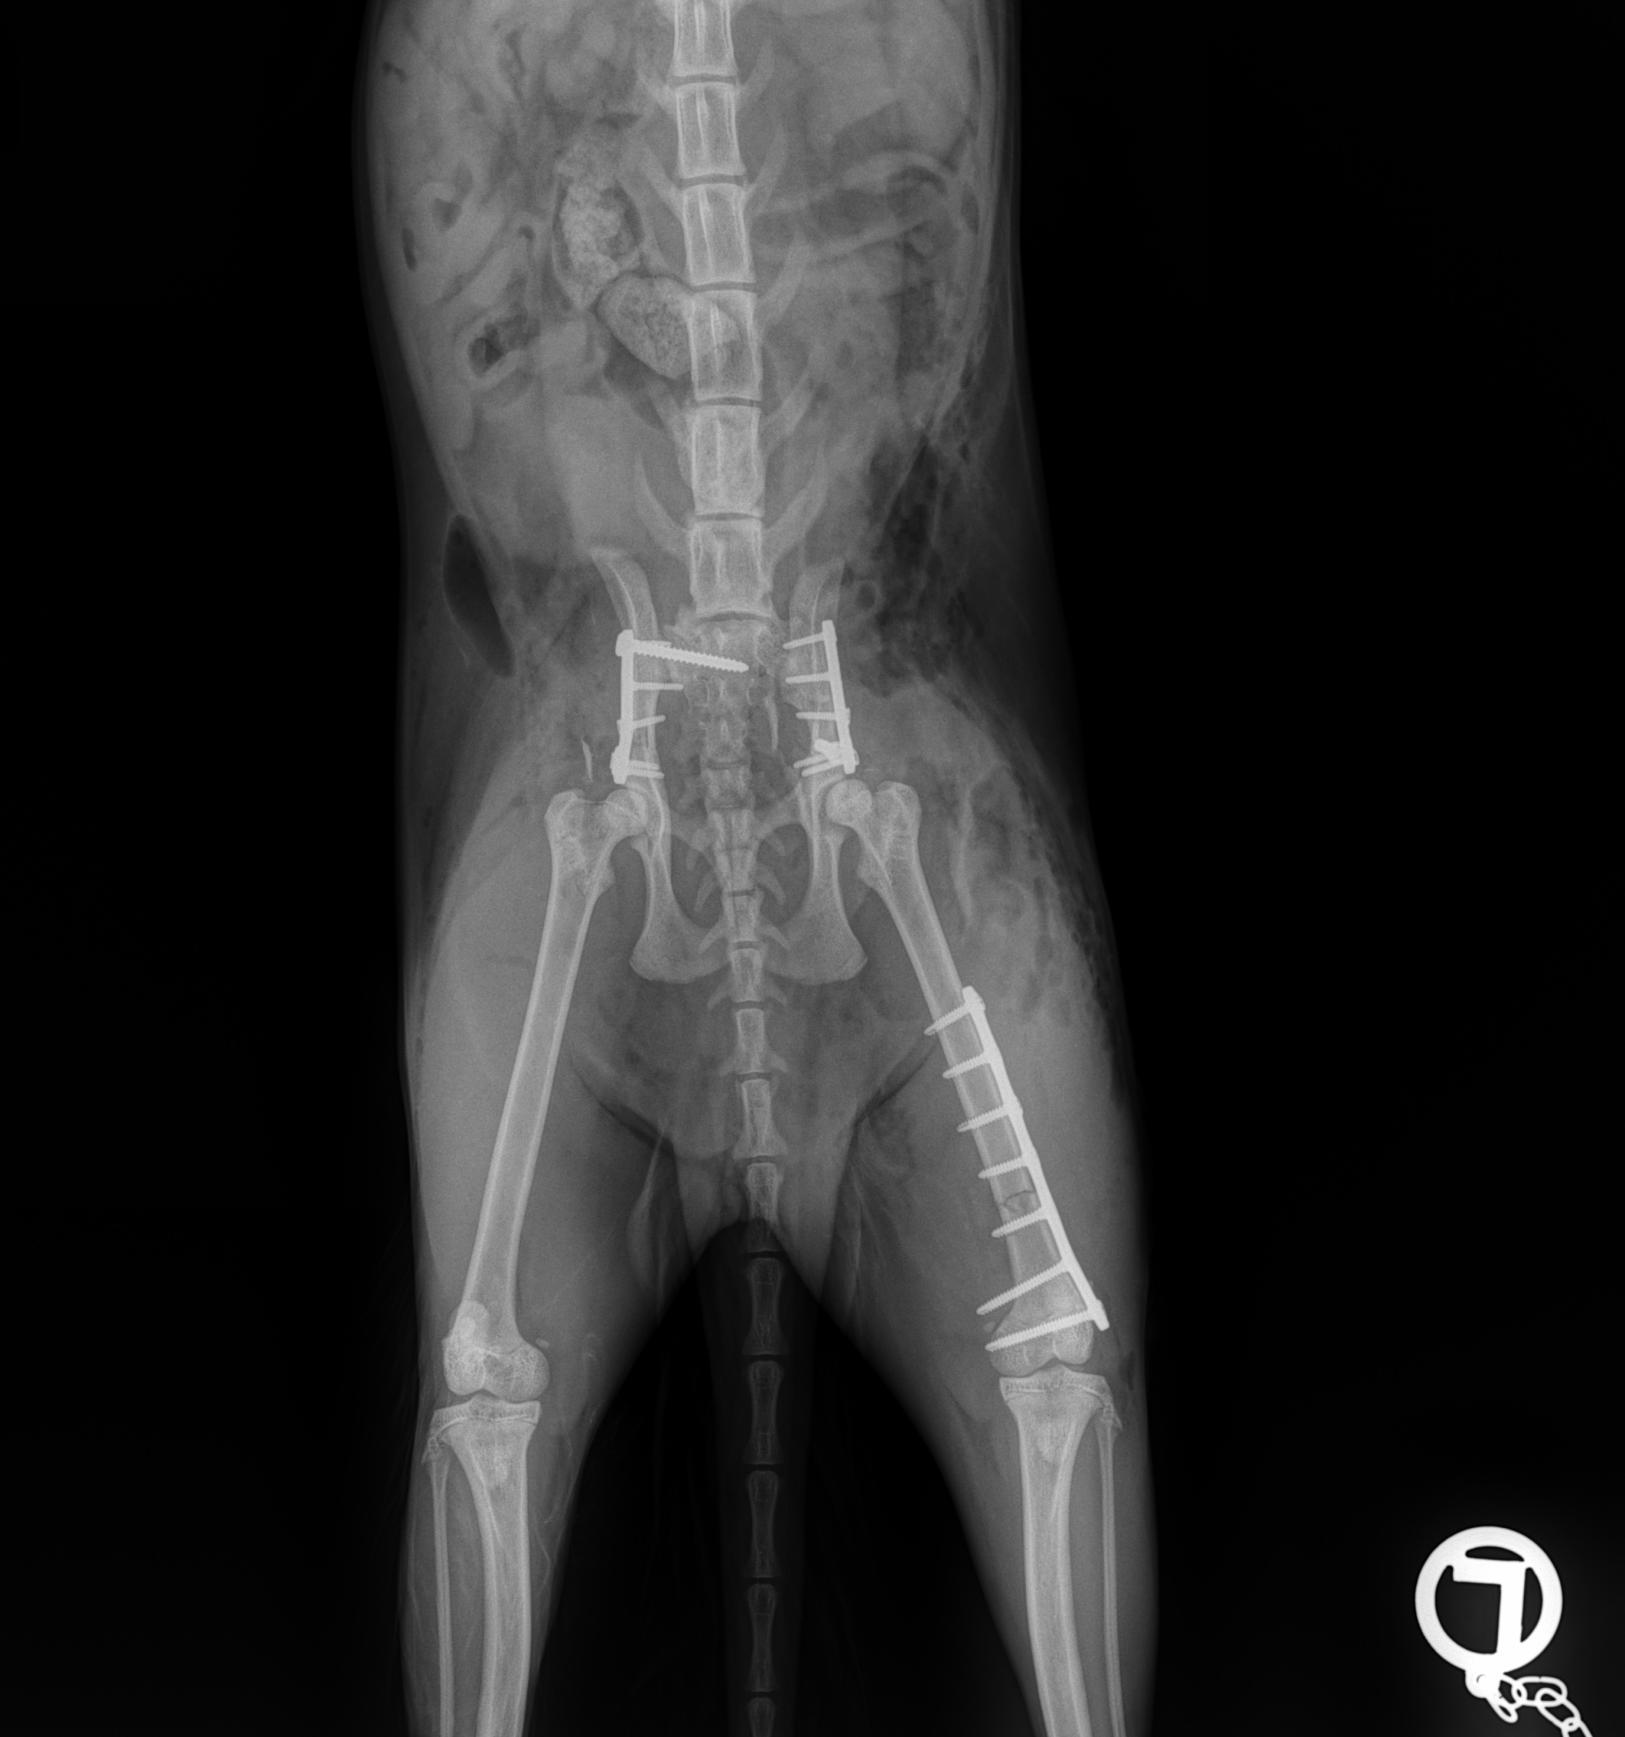

Fracture Treatment in Small Breeds:

Experience of 100 Cases

CrCL Ruptures in Small Breeds:

Osteotomies or extra capsular repair

CrCL Ruptures in Small Breeds: Should we use osteotomies instead of extra capsular repair?

TTA RAPID®

Learn how to perform CCL Repair with TTA RAPID®

Tiny TTA RAPID®

Learn how to fix CCL Ruptures in Tiny Animals with the Tiny TTA RAPID® System

Rapid Luxation

Learn how to fix Patella Luxation with the RAPID LUXATION System